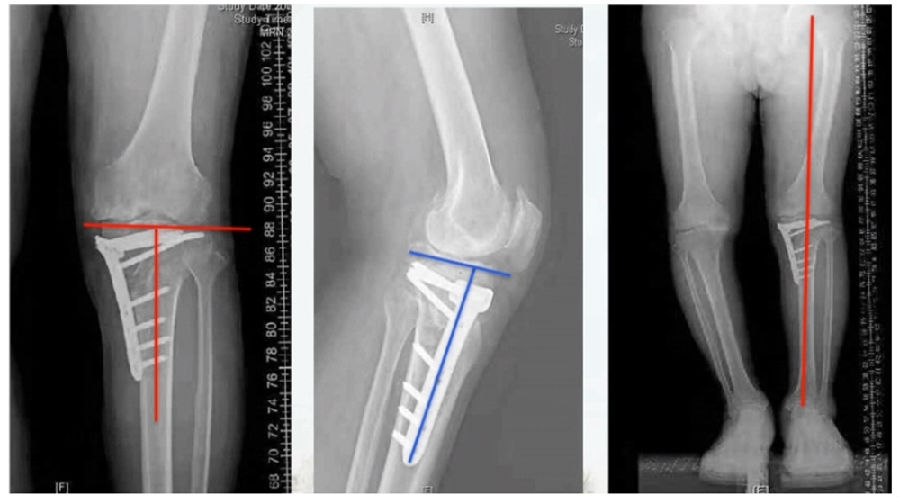

该患者截骨后,做MAD矫正,目标MAD=0。患者术后1个月即达到设计的效果。

术后1个月

股骨畸形即时矫正,胫骨畸形缓慢矫正。

术中

手术前后对比